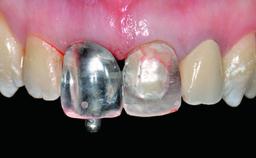

Abutment Type CAD/CAM

Prosthesis Type FDP

Loading Protocol Conventional or early

Retention Screw-retained Screw-retained

Provisional Implant-Supported Prosthesis - -

Interim Prosthesis during Healing Removable Removable